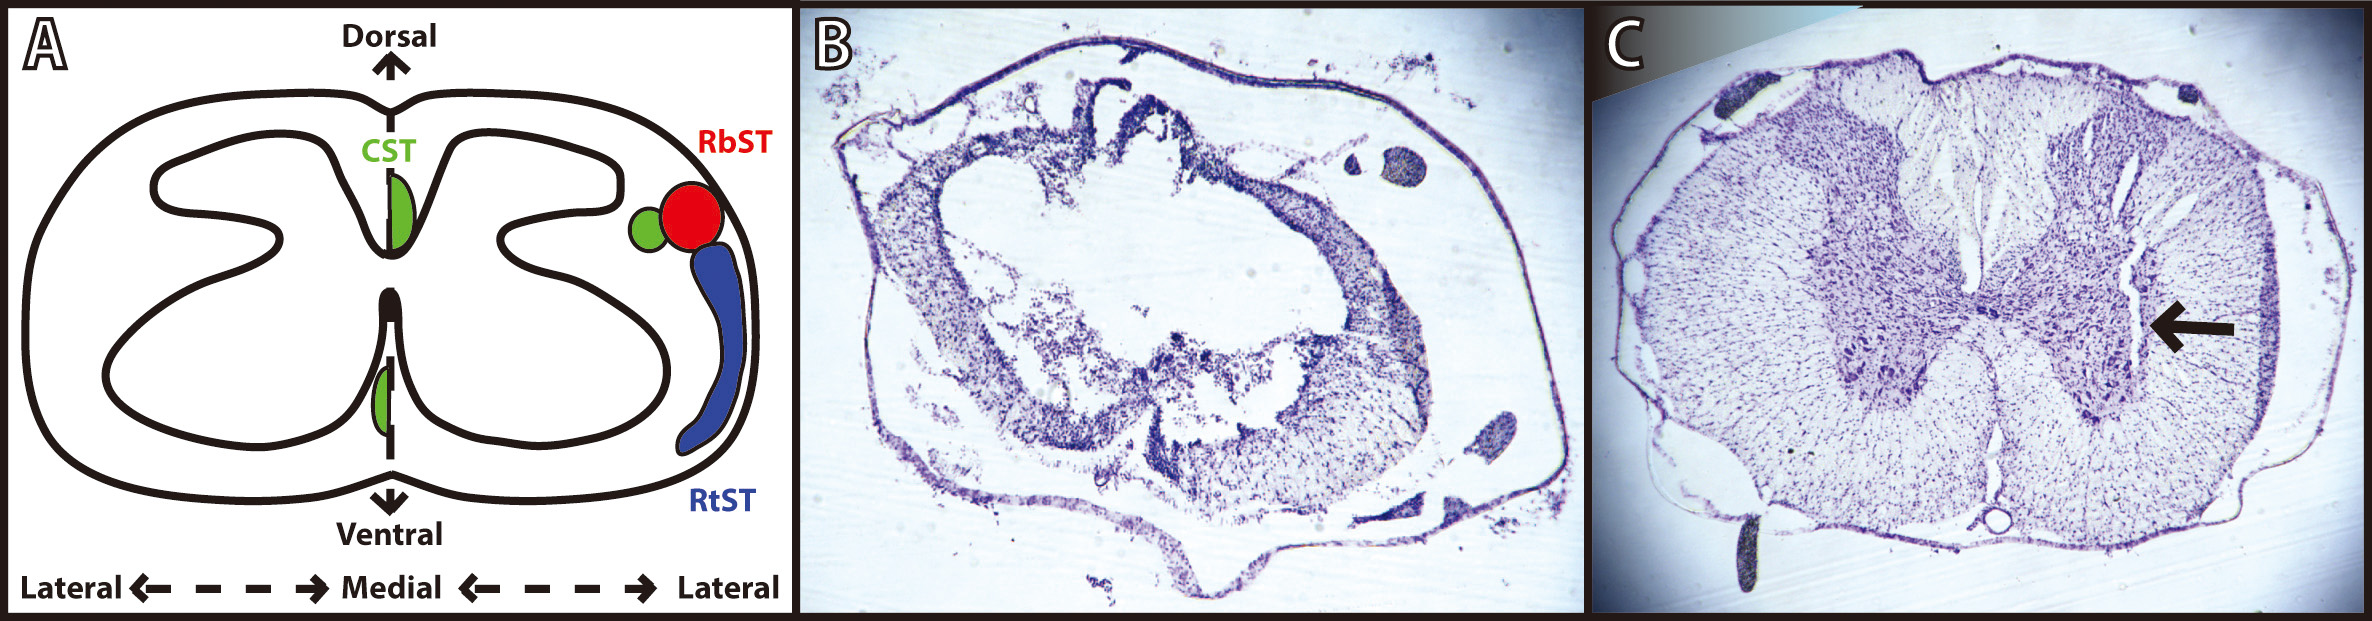

Fig. 3.Verification of spinal cord injury and microwire implantation. (A) Schematic diagram of a coronal thoracic section identifying the location of the descending corticospinal tract (CST; green), rubrospinal tract (RbST; red), and reticulospinal tract (RtST; blue). Reproduced with permission from Roger N. Lemon, Descending Pathwaysin Motor Control; published by Annual Reviews, 2008. [22]; and reproduced with permission from Kathren L. Fink, Reorganization of Intact Descending Motor Circuits to Replace Lost Connections After Injury; published by Springer, 2016. [23]. (B) Representative image of spinal cord injury epicenter under T8 vertebrae stained with cresyl violet 8 weeks after injury. (C) Representative image of microwire implant track under T13 vertebrae stained with cresyl violet 4 weeks after implantation.

While the anatomical substrate for recovery after ADS remains speculative, and was not examined in the present study, it may be useful to consider the putative role(s) of spared pathways for design of follow-on studies. Three descending spinal cord pathways provide substantial influence on hindlimb motor function in the rat: the corticospinal tract (CST), the rubrospinal tract (RbST), and the reticulospinal tract (RtST). Crossed corticospinal axons, traveling in the dorsal columns in rats, are severely damaged using the present contusion model over a wide range of contusion severity [27]. Based qualitatively on the location of white matter observed in post-mortem histological sections, the RbST and dorsolateral CST (dCST) in the dorsolateral funiculus, the RtST and ventromedial CST (vCST) in the ventral funiculus, and many propriospinal fibers (both descending and ascending) likely remained at least partially intact after the moderate bilateral contusion injury used in this study (Fig. 3). Spared fibers in these pathways may be viable therapeutic targets for strengthening of connectivity from cortex to the lumbar cord to enhance the recovery of voluntary movement.